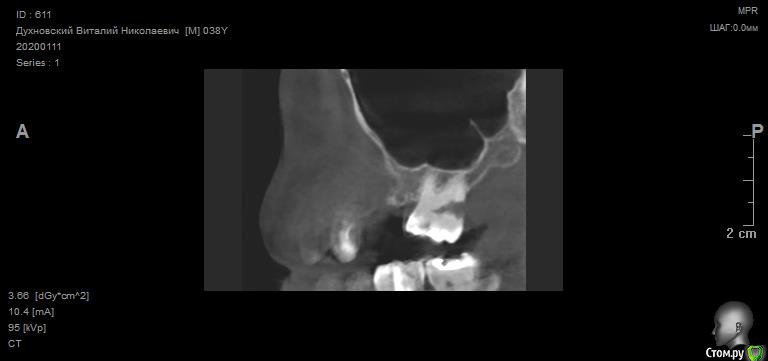

Просьба ко всем не равнодушным! Глянуть КТ верхней челюсти, 27 зуб  и место где удалили 16, может ещё где-то могут быть проблемы.  На фото видно где покраснение на дёснах, в этих местах возникают боли при движении головой. Бывает боль слева если засыпаю на левой стороне. Набуханий или флюсов нигде не видно.Прошу делиться мнениями, для меня это очень - очень важно. Стоматолог визуальных проблем на месте удалённого зуба не видит, всё зажило.

температура иногда бывает 37.2. ну чувствую себя как будто 38.5.по общему анализу крови было без особых отклонений. Может ли после удаления зуба долго идти  не заметный вялотекущий воспалительный процесс в десне?  Может 27 является источником инфекции? Там на снимке видна скрытая полость.

По данным КТ в зоне удалённого зуба 16 ничего особенного, разве что, ретенированный (непрорезавшийся) зуб 18.

Зуб 27 требует внимания, необходим очный осмотр.